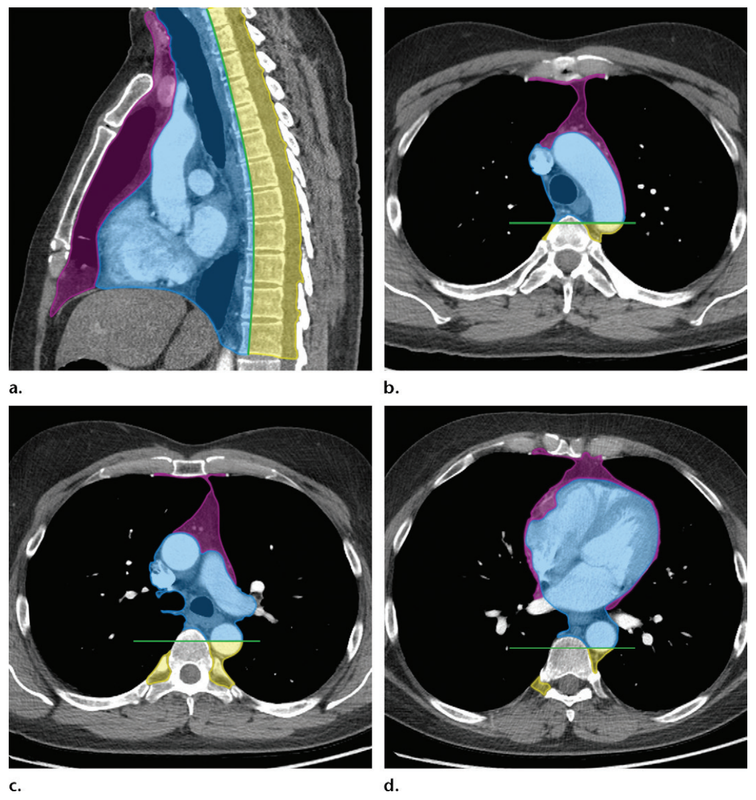

隨著胸部CT被廣泛應(yīng)用于肺部疾病鑒別診斷及常規(guī)體檢,縱隔腫瘤檢出數(shù)目也逐漸隨之升高。排除流行性呼吸系統(tǒng)病毒感染爆發(fā)影響,每年縱隔腫瘤患者常在入學(xué)、入伍、入職體檢時(shí)段檢出就醫(yī),故也成為“高考瘤”、“入伍瘤”或“入職瘤”。根據(jù)解剖部位分布,縱隔腫瘤分為前、中、后;上、中、下區(qū)域。鑒于縱隔腫瘤疾病種類(lèi)繁多,涉及胸腺來(lái)源、胸膜來(lái)源、神經(jīng)來(lái)源、胚胎來(lái)源(畸胎瘤)、甲狀腺來(lái)源、骨髓來(lái)源、淋巴系統(tǒng)來(lái)源等多個(gè)器官或系統(tǒng),故鑒別診斷較為困難,多數(shù)情況下確診需要依靠切除活檢后的病理診斷結(jié)果。如果條件允許,術(shù)前CT或者超聲引導(dǎo)下細(xì)針穿刺活檢看提供重要診斷依據(jù)。中青年人群是縱隔腫瘤好發(fā)群體,初次發(fā)現(xiàn)建議結(jié)合多模態(tài)影像學(xué)檢查評(píng)估,主要指增強(qiáng)CT聯(lián)合MRI。此外,全身PET-CT有助于明確胸外病灶分布,常協(xié)助臨床醫(yī)生尋找原發(fā)腫瘤,或者輔助診斷淋巴瘤。以胸腺上皮來(lái)源腫瘤(俗稱(chēng)胸腺瘤)為例,動(dòng)態(tài)觀察期間發(fā)生顯著變化,或者初診時(shí)影像學(xué)評(píng)估邊界不清則應(yīng)警惕惡性腫瘤可能。盡早外科干預(yù)以避免腫瘤惡化外侵導(dǎo)致無(wú)法根治性切除。通常情況下,直徑<1cm的縱隔腫瘤可考慮定期隨診,動(dòng)態(tài)評(píng)估腫瘤變化,推斷腫瘤生物學(xué)行為特征以鑒別良惡性。少數(shù)情況下,也可以通過(guò)微創(chuàng)外科方式完整切除以清除疾病與精神負(fù)擔(dān),然而外科干預(yù)的利弊需要術(shù)前充分同患者及家屬交流,獲得知情同意。上圖病例則是1例少見(jiàn)的青年型早期胸腺鱗癌患者,經(jīng)微創(chuàng)外科治療后術(shù)后病理診斷為I期胸腺鱗癌,術(shù)后定期隨診無(wú)復(fù)發(fā)轉(zhuǎn)移征象。個(gè)人經(jīng)驗(yàn)更傾向通過(guò)動(dòng)態(tài)觀察評(píng)估腫瘤影像學(xué)倍增時(shí)間以輔助診斷,唯有敬畏腫瘤疾病本身,在先進(jìn)科技的“仙人指路”下,充分發(fā)揮各個(gè)棋子的特色優(yōu)勢(shì),才能實(shí)現(xiàn)“帥士無(wú)損,所向無(wú)敵”。